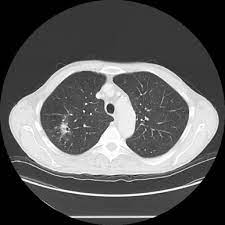

Pulmonary tuberculosis is caused by mycobacterium tuberculosis, which produces characteristic tuberculosis changes in the lung. Tuberculosis infection should be based on the reasons and the context for testing, test availability, and overall cost. Lung cancer, also known as lung carcinoma, is a malignant lung tumor characterized by uncontrolled cell growth in tissues of the lung. Tuberculosis is curable and preventable. Most lung cancers do not cause any symptoms until they have spread, but some people with early lung cancer do have symptoms.

Lung Cancer And Pulmonary Tb Youtube from i.ytimg.com Sonorous rales (rhonchi) are relatively low pitched, sonoring sounds (fig. Tuberculosis (tb) is a potentially serious infectious disease that mainly affects the lungs. The occurrence of pulmonary tuberculosis (ptb) and lung cancer as comorbidities has been extensively discussed in many studies. There is especially in countries with low tb incidence diagnostic challenges with risk of diagnosis getting missed. When people with lung tb cough, sneeze or spit, they propel the tb germs into the air. Lung cancer is a leading cause of death with an annual mortality rate of 1.59 million people, accounting for 19.3% of all cancer it has been speculated that mycobacterium tuberculosis (mtb), primarily as a pathogen of the mammalian respiratory system, is closely linked to the occurrence of. Tuberculosis (tb) is a contagious infection that usually attacks your lungs. Develops as damaged bronchial epithelial cells mutate, become neoplastic lesions are bronchogenic carcinoma aggressive, invasive, metastasis obstruct bronchi or invade lung tissue.

How Tuberculosis Is Diagnosed Everyday Health from images.everydayhealth.com Tuberculosis (tb) is a potentially serious infectious disease that mainly affects the lungs. The occurrence of pulmonary tuberculosis (ptb) and lung cancer as comorbidities has been extensively discussed in many studies. When people with lung tb cough, sneeze or spit, they propel the tb germs into the air. In the past, it was well known that lung cancer is a specific epidemiological successor of ptb and that lung cancer often develops in scars caused by ptb. Lung cancer is often divided into two types: Difference between lung cancer and tuberculosis. Tb disease most commonly affects the lungs and is referred to as pulmonary tb disease. Tuberculosis (tb) is caused by bacteria (mycobacterium tuberculosis) that most often affect the lungs.

Symptoms of tuberculosis and lung cancer are overlapping and it is difficult to differentiate without the histopathological report. This study compares the survival and immunological cell profile in tblc over nsclc alone. To clarify the clinical and survival characteristics of cases with both lung cancer and active pulmonary tb.design. In the past, it was well known that lung cancer is a specific epidemiological successor of ptb and that lung cancer often develops in scars caused by ptb. Lung cancer and tuberculosis (tb).

This study compares the survival and immunological cell profile in tblc over nsclc alone. Lung cancer, also known as lung carcinoma, is a malignant lung tumor characterized by uncontrolled cell growth in tissues of the lung. Pulmonary tb is caused by the bacterium mycobacterium tuberculosis (m tuberculosis). When people with lung tb cough, sneeze or spit, they propel the tb germs into the air. Lung cancer and pulmonary tuberculosis (tb) comorbidity is a clinical problem that presents a challenge for the diagnosis and treatment of both diseases.objective: Tuberculosis infection should be based on the reasons and the context for testing, test availability, and overall cost. Is it possible for the doctor to mistake a possible lung cancer for tb? Lung pathology of fatal severe acute respiratory syndrome. Sclc is characterized by its central location, rapid tumor. Tuberculosis (tb) and lung cancer are important global health threats, each accounting for 1.6 million deaths yearly. Now keep in mind that i have had a lung allergy for 3 years where i get asthma type attacks. Pulmonary tuberculosis is caused by mycobacterium tuberculosis, which produces characteristic tuberculosis changes in the lung. Tb is spread from person to person through the air.